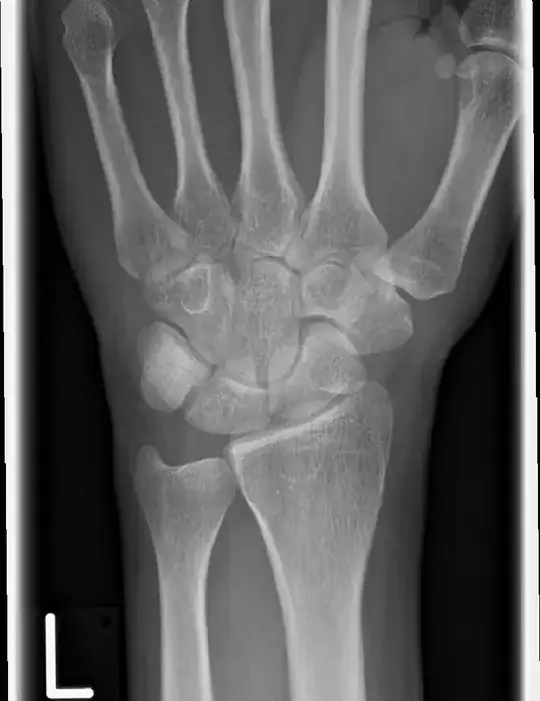

I'm a medical student. As an exercise, we got an x-ray photograph of the left hand of a patient who reports to have fallen onto this hand, and has pain at the location of the scaphoid bone. The question we have to answer is whether there might be a fracture and what to do next for the diagnosis. On the photograph, I don't see any fracture and I would simply say there is no fracture and tell the patient to wait and see. Is this too simple?

left hand

I also don't see any fracture in the scaphoid, but "fractures of the scaphoid are not visible in about 16% of cases on initial radiographs" (Clinical scaphoid fracture, PubMed, 2011).

When symptoms suggest scaphoid fracture, but no fracture is seen on a radiograph, the current approach is to consider it as a "clinical scaphoid fracture," immobilize the wrist and take another radiograph after 14 days. The article linked above criticizes this approach and recommends performing an early CT, MRI or scintigraphy to rule out other causes, such as distal radius fracture and tendon strain (see also aafp.org, Table 1).